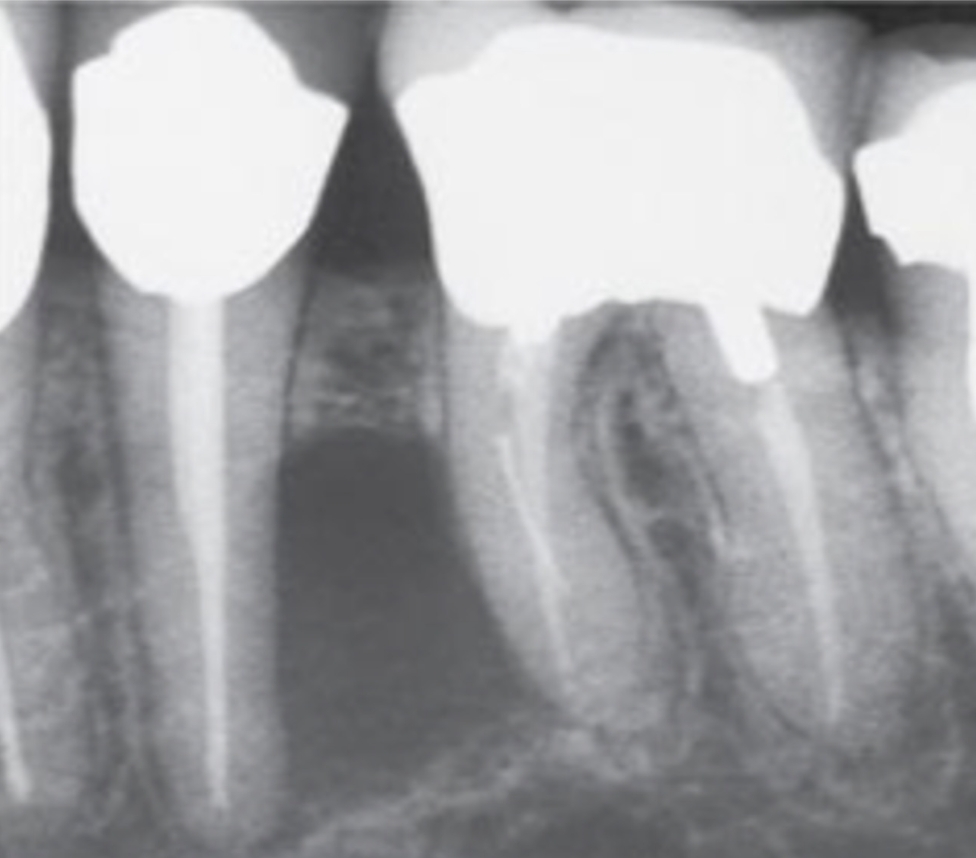

dense, reactive bone formation → radiopacity around periapical lesions

rarefying vs sclerosing osteitis

rarefying → increased radiolucency

sclerosing → increased radiopacity

idiopathic osteosclerosis / dense bone island

can mimic sclerosing osteitis (condensing osteitis)

PDL space remains uniform